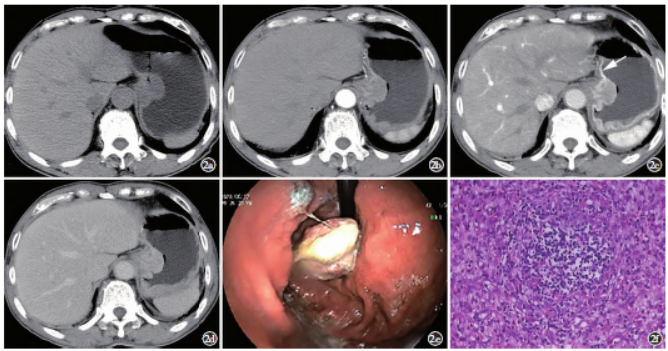

病例2,男,70岁,半年前无明显诱因出现进食后胸骨后疼痛不适伴嗳气,2周前症状加重,食欲下降,心慌乏力,体重减轻9kg。实验室检查无特殊。查体:全腹无压痛及反跳痛,无肌紧张,未触及肿块。上腹部CT检查见胃底贲门部黏膜下稍低密度肿块,呈分叶状,大小约4.1cm×3.8cm,增强三期呈渐进性强化,病灶周围胃黏膜增厚且强化明显(图2a~2d),CT诊断胃间质瘤。胃镜检查示胃底近贲门处黏膜隆起溃烂(图2e)。

全麻下腹腔镜下行胃近端切除术,术后大体病理示胃小弯侧黏膜下见隆起,切面灰红,实性,质软;镜下示黏膜下层、肌层见梭形、肥胖的肌纤维母细胞疏松排列,弥漫性浆细胞、嗜酸性细胞浸润,灶性淋巴细胞聚集,并多量血管增生(图2f)。免疫组化:CD34(-)、ALK(-)、SMA(-)、DES(-)、CD117(-)、DOG-1(-)、S-100(-)、STAT6(-)、MyoD1(-)、Ki-67(+约10%)。病理诊断:胃部炎性肌纤维母细胞瘤。患者术后随访至今,未见复发及转移灶。

图2病例2。a)上腹部CT平扫b)增强动脉期;c)静脉期;d)延迟期轴位示胃贲门小弯侧肿块,分叶,平扫呈稍低密度影,中度渐进性强化,强化均匀;c)邻近胃黏膜增厚强化明显(箭);e)胃镜图;f)镜下病理图(HE染色,×100)